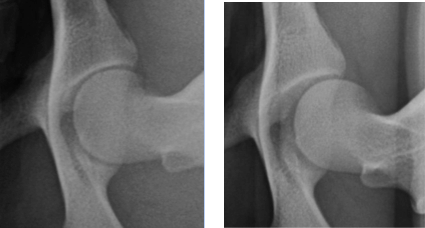

Bei der Distraktionsaufnahme wird ein sogenannter Distraktor zwischen die Beine des Tieres gelegt. Wenn der Untersucher die Beine des Hundes gegen den Distraktor drückt, wird der Oberschenkelkopf aus der Hüftpfanne „herausgezogen“. Je weiter das möglich ist, desto lockerer ist die Hüfte und desto größer die Wahrscheinlichkeit, dass ein Hund an einer HD leiden wird. Das Maß für die Lockerheit des Hüftgelenks ist dabei der Distraktionsindex (DI).

links: komprimiertes Hüftgelenk

rechts: distrahiertes Hüftgelenk

Berechnung des Distraktionsindex

(Quelle: AIS PennHIP®)

Der Distraktionsindex wird berechnet, indem bei der Distraktionsaufnahme die Entfernung zwischen dem Mittelpunkt des Oberschenkelkopfes und dem Mittelpunkt Hüftpfanne gemessen und diese Strecke durch den Radius des Oberschenkelkopfes geteilt wird. Dabei kann der Index von 0 bis 1,0 betragen. Bis zu einem Distraktionsindex von 0,3 ist die Wahrscheinlichkeit, dass sich das Krankheitsbild einer HD entwickelt, äußerst gering. Bei Rassen wie z.B. dem Barsoi oder dem Greyhound ist ein solcher DI üblich. Bei diesen Rassen entwickelt sich im Verlaufe des Lebens im Regelfall nicht das Krankheitsbild einer HD.

Bei höheren Werten muss hingegen mit einer HD und entsprechenden Gelenksveränderungen (Arthrosen) gerechnet werden.